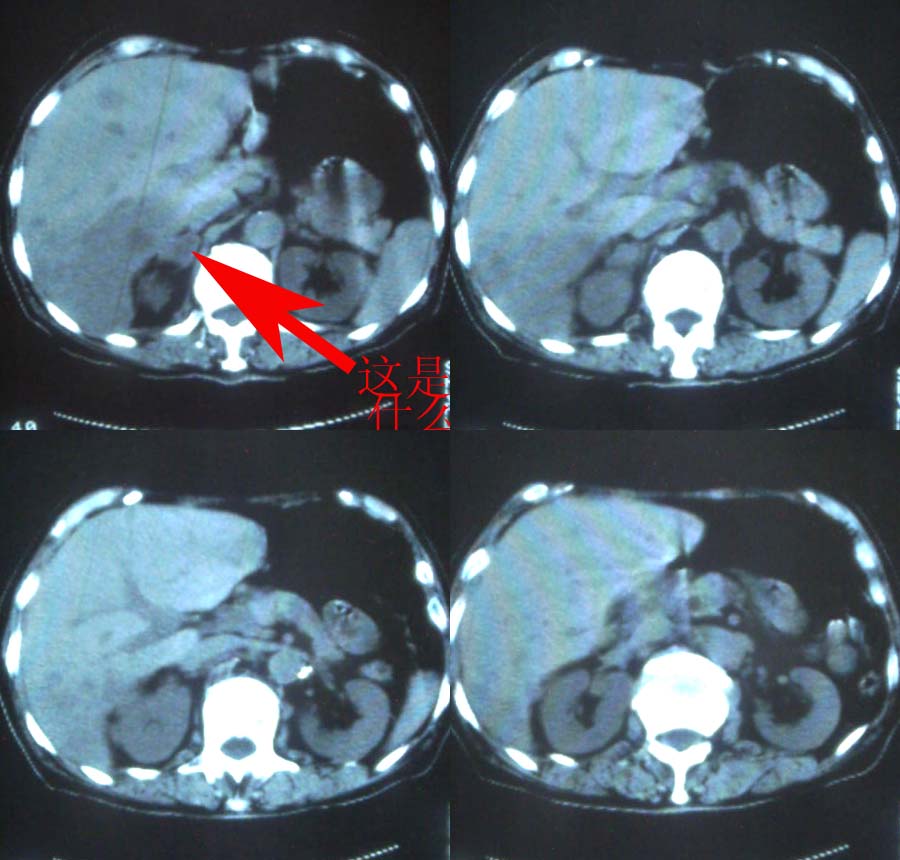

各位老师见笑 请问右侧肾上腺为啥考虑为转移灶?

1、分析:(1)女性75岁;(2)单侧大量胸腔积液;(3)右侧肺门区团块影,单纯的压迫性肺不张?肿块?;(4)肝脏内多发结节影,大小不等,多结节型肝癌?肝癌并肝脏内转移?(5)肝脏内结节病灶中心有更低密度区;(6)右侧肾上腺不规则软组织灶;(7)肝脏各叶比例正常,脾脏不大。

关于牛眼征我记得好象是血液供应不上而坏死吧?其并不是肝转移瘤专利。

看看下面是不是牛眼征:

右肾上腺转移瘤